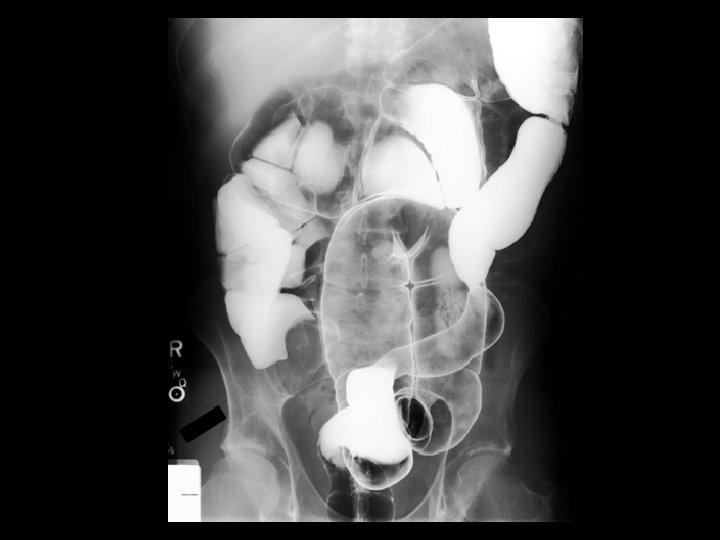

Intussusception • Findings: – Low density intraluminal mass within a small bowel loop – Contrast surrounding this mass produced the “coil spring” appearance – Associated with a lead point in adults: • Lipoma • Carcinoma • lymphoma • Meckel’s diverticulum